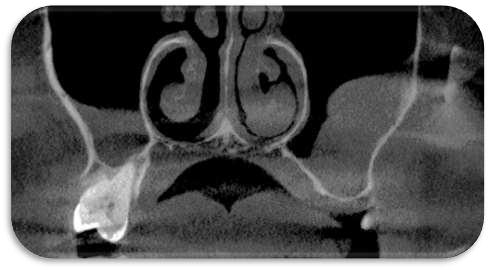

FIGURA 1 (TOMOGRAFIA VISTA FRONTAL)

En el corte tomográfico oblicuo–sagital derecho se observa: (figura 3)

Imagen hipodensa, bien delimitada, de contorno redondeado, ubicada en el seno maxilar derecho.

La lesión parece originarse desde el piso del seno, con íntima relación con los ápices dentarios superiores posteriores.

No se aprecian signos de erosión ósea marcada, aunque existe adelgazamiento del piso sinusal

La densidad es homogénea, lo que orienta hacia un contenido quístico

Conclusión

Seno maxilar derecho: ocupándolo parcialmente, se identifica una imagen hipodensa, bien delimitada, de contorno redondeado y homogéneo, compatible con lesión quística

Produce expansión con adelgazamiento de la pared ósea sin clara evidencia de destrucción.